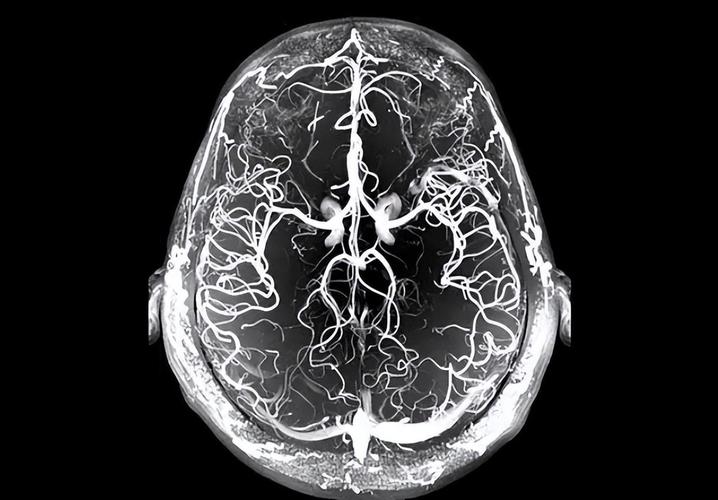

当然可以,脑部磁共振(MRI)是诊断腔隙性脑梗死最敏感、最准确的首选影像学检查方法。

为什么脑MRI能查出腔隙性脑梗死?

脑MRI之所以对腔隙性脑梗死如此敏感,主要得益于其独特的成像序列和技术优势:

- 极高的软组织分辨率:MRI对大脑组织的细微变化非常敏感,能清晰分辨脑白质、灰质、脑脊液等不同结构,即使是几毫米的小病灶也能被发现。